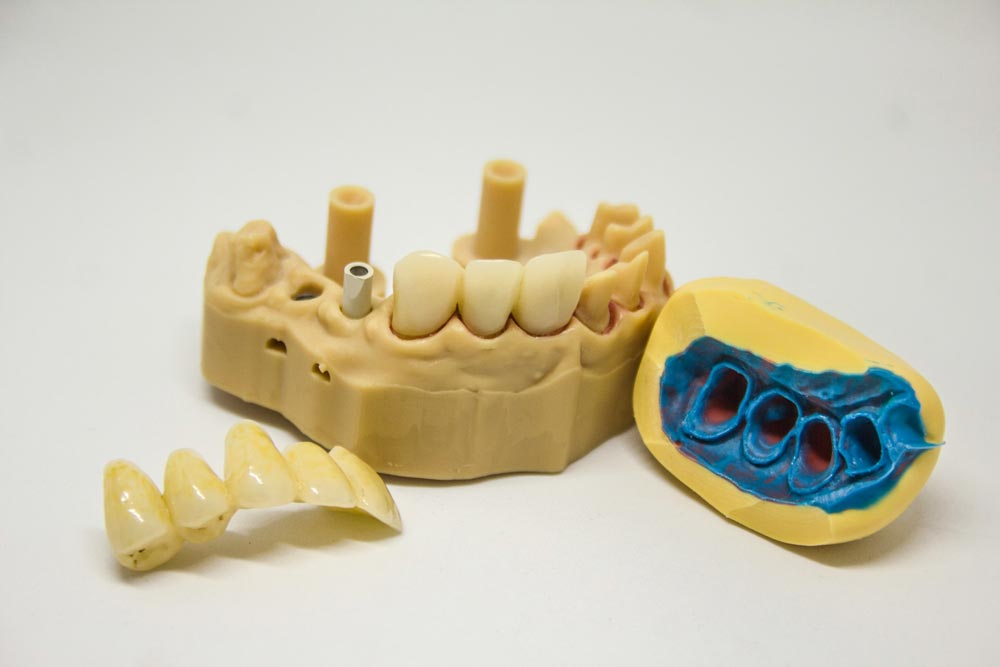

「好牙齒,種出來」「無痛種牙,即種即用」……無論是地鐵,還是公車站,或是社區電梯裡,常常都會出現這類廣告。 還有一些缺牙的朋友,去醫院都有類似的經歷,想修復缺牙時,醫生基本上都會推薦做植牙。 可是一問價格,卻發現差異還特別大,有的一顆就上萬,便宜些的幾千塊。

但不管怎樣,這都是一筆不小的費用,於是大家的疑問便來了:缺牙了就不能拖一拖? 就只能種牙嗎? 還是醫生為了讓我們多花錢? 這個差價究竟體現在哪裡? 難道真的是“一分錢一分貨”,貴的就一定比便宜的好? 既然都花了這麼多錢,這顆植牙是能讓我用一輩子嗎? 畢竟種牙不像買賣快消品,可以先試再買。 你到底能不能種? 種之前需要了解好哪些資訊才不至於被坑呢? 今天的文章一一給大家展開說說。